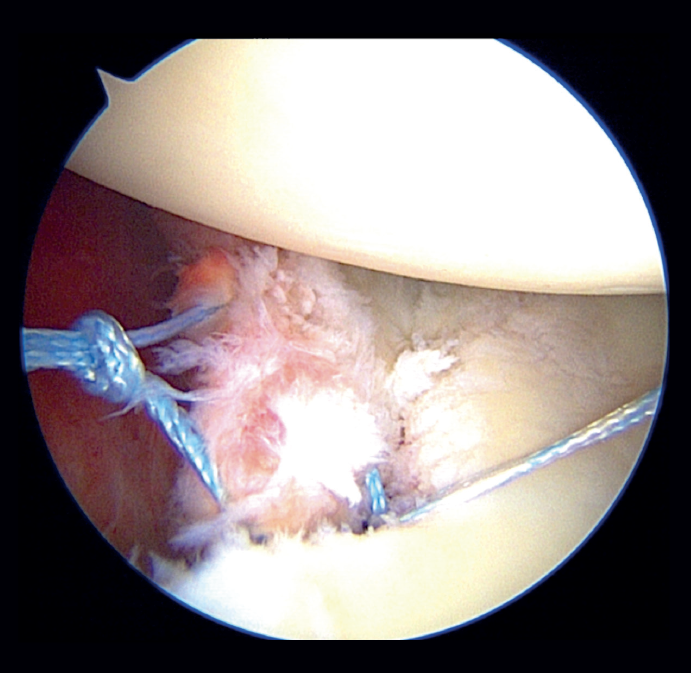

In the classical Porcellini-Sugaya technique, debridement and roughening of the bone margins of the fracture was carried out with synoviotome, rasps and curettes (Figure 2). All-suture anchorings were used for the repair. The first anchoring was placed in the lowermost zone of the defect (Figure 3), and one its extremities extended to the damaged labrum in the lowermost zone, followed by knotting. The second anchoring was placed in the uppermost zone of the defect (Figure 4), in the same way as the first, followed by knotting. In those cases where considered necessary, one or two more anchorings were added proximal to the previous ones. Reduction and stability of the fragment was checked.

In the modified double-row/double pulley technique, and in addition to the measures commented above, an anchoring was added between the first implant and the second, at the height of half of the fractured bone fragment but in a position medial with respect to the chondral margin of the glenoid cavity (Figure 5). In this case, both the extremities crossed through the capsule at the level of half of the fragment and anterior to the latter at different points, followed by knotting and maintaining reduction of the bone fragment (Figure 6). One of the extremities of the suture knot made was tied to one of the extremities of the lower anchoring, while the other was tied to one of the extremities of the upper anchoring, thereby completing the repair procedure (Figure 7).